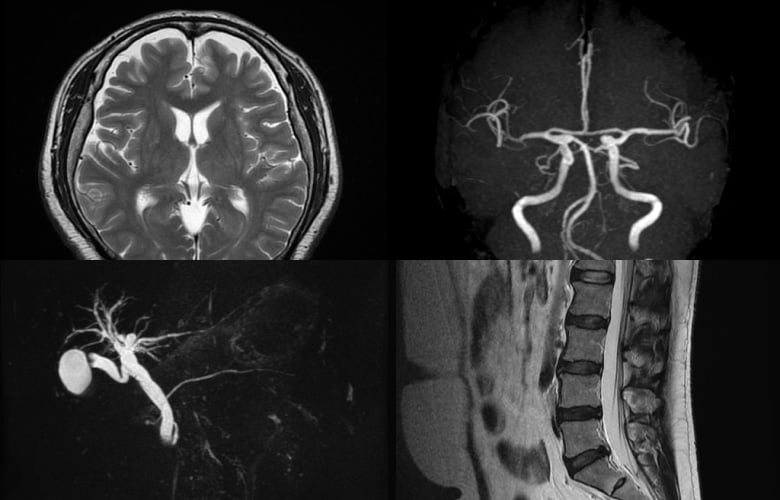

MRI検査について

近隣の医療機関の先生方のご依頼にてMRI検査を行うことができます(単純検査のみ)。

GEヘルスケア製 1.5T

検査可能部位

• 頭部: 頭部 / 視神経 / 聴神経 / 副鼻腔 など

• 頸部: 咽頭 / 喉頭 / 口腔 / 舌 / 甲状腺 など

• 脊椎: 頚椎 / 胸椎 / 腰椎 / 仙椎

• 腹部: 肝胆膵(MRCP) / 腎臓 など

• 骨盤: 骨盤骨 / 股関節 / 前立腺 / 膀胱 / 子宮 / 卵巣 など

• 関節: 肘関節 / 膝関節 / 足関節 など

• その他: 手 / 足 など